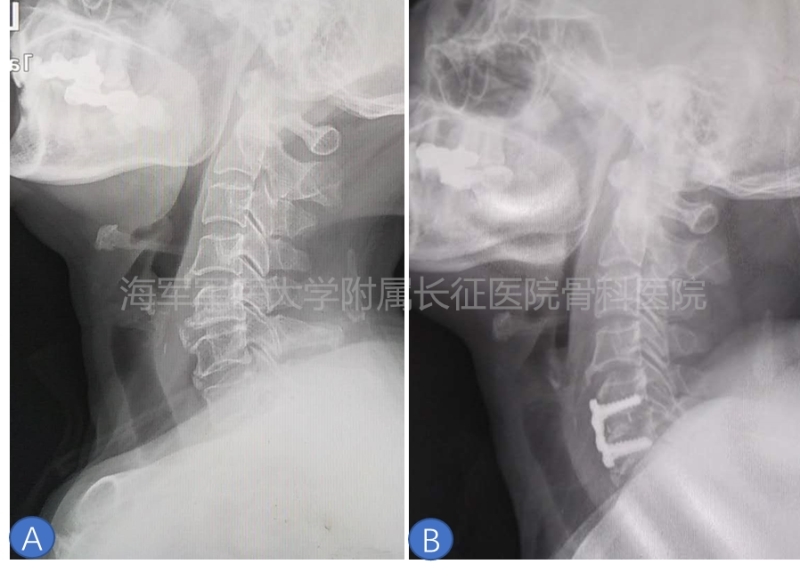

图4 ACDF恢复自然高度。A.患者术前X线侧位片;B.单节段ACDF术后恢复C5/6高度至自然高度